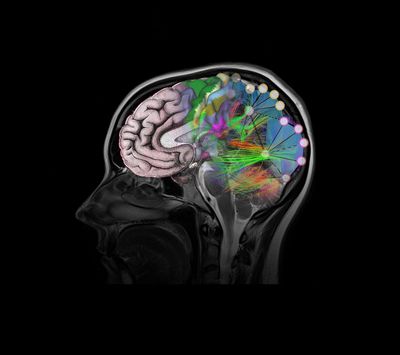

If you ever have the chance to look at a human brain outside the protective dome of the skull, you’ll find it looks distinctly… gray. And wet. But mostly gray. This color is almost irrevocably linked with the brain, perhaps most famously by Agatha Christie’s protagonist Hercule Poirot, who talked of his “little gray cells” that helped him solve the most perplexing mysteries. But our fixation on the gray can sometimes lead us to ignore a second type of brain tissue, one that lies just beneath: the white matter.

The below image shows a formaldehyde-fixed human brain, viewed from above. Specifically, what we’re looking at here is the gray matter. The troughs winding across the surface are called sulci, and the corresponding ridges are called gyri.

Now, if we slice the brain open, you can see a slightly darker line of demarcation running all around the outside edge. The lighter-colored tissue below that line is the white matter. There’s also a whacking great hole, but we’ll get to that later.